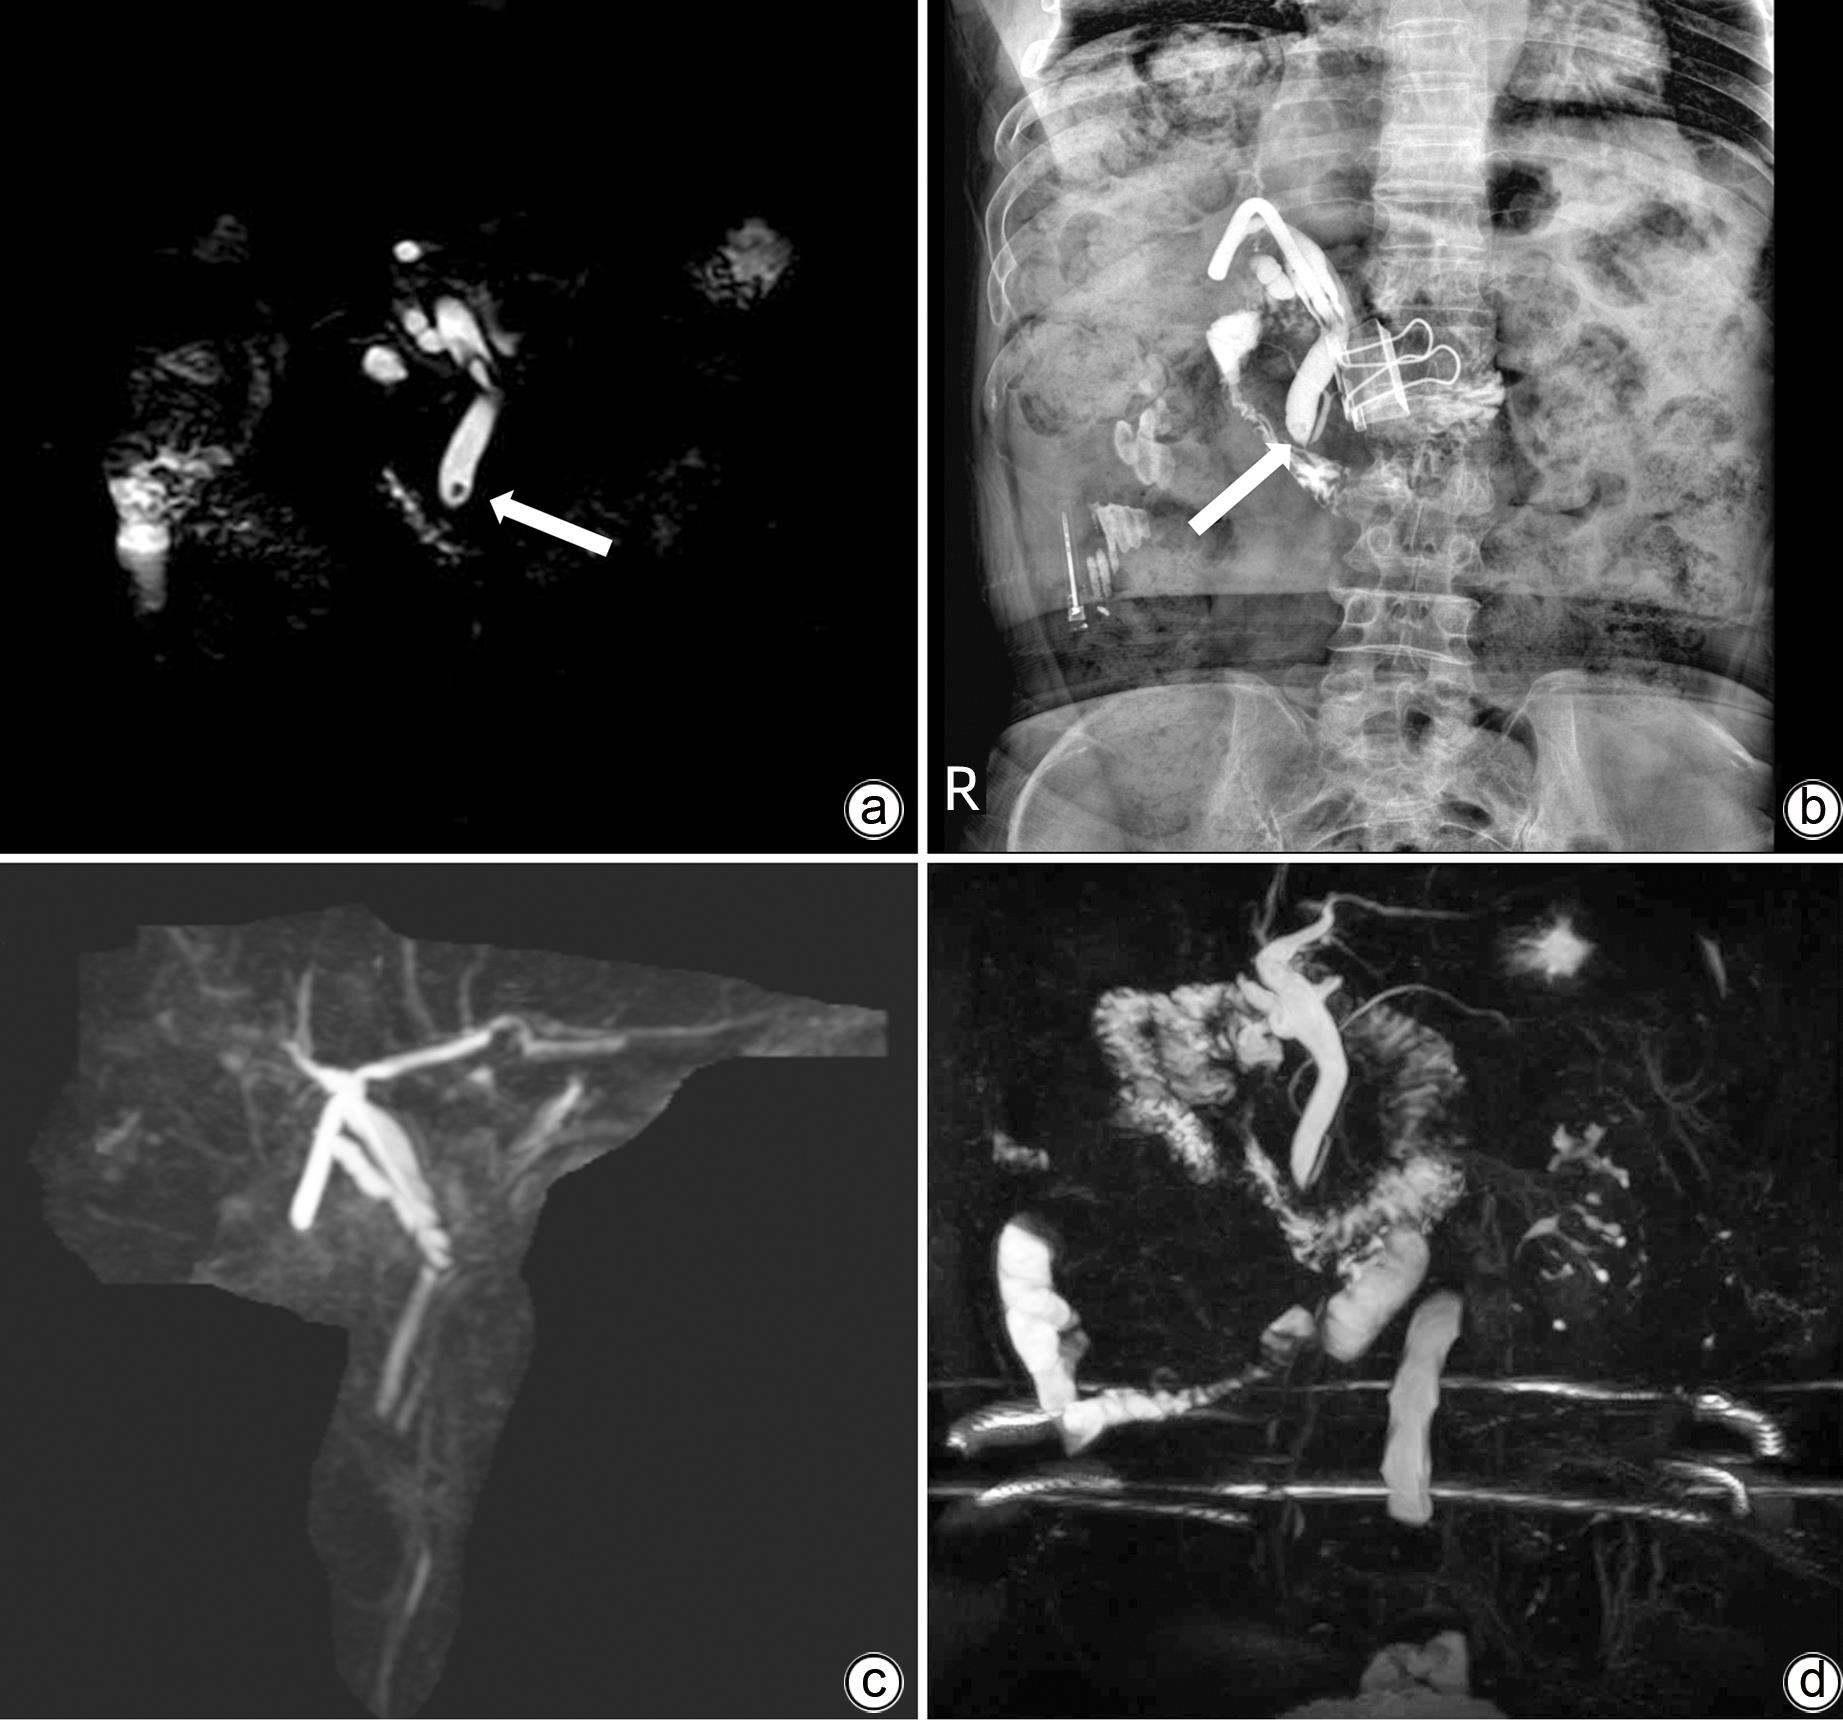

• At present, endoscopic retrograde cholangiopancreatography (ERCP) and T-tube sinus tract lithotomy are the main treatment methods for residual choledocholithiasis after surgery. However, these treatment methods have certain drawbacks; for example, ERCP may cause complications such as postoperative pancreatitis, bleeding, and perforation, and T-tube sinus tract lithotomy may cause sinus tract injury and bleeding. As a commonly used instrument in urology, flexible ureteroscope has the characteristics of small diameter and flexible angle and thus has a good prospect in the treatment of common bile duct stones. A patient with common bile duct stones was successfully treated by flexible ureteroscopy combined with a stone basket in Department of General Surgery, The Second People’s Hospital of Guizhou Province. Up to now, the patient has been followed up for seven months with no special discomfort, and magnetic resonance cholangiopancreatography showed no common bile duct stones.

Figures(1)  / Tables(1)